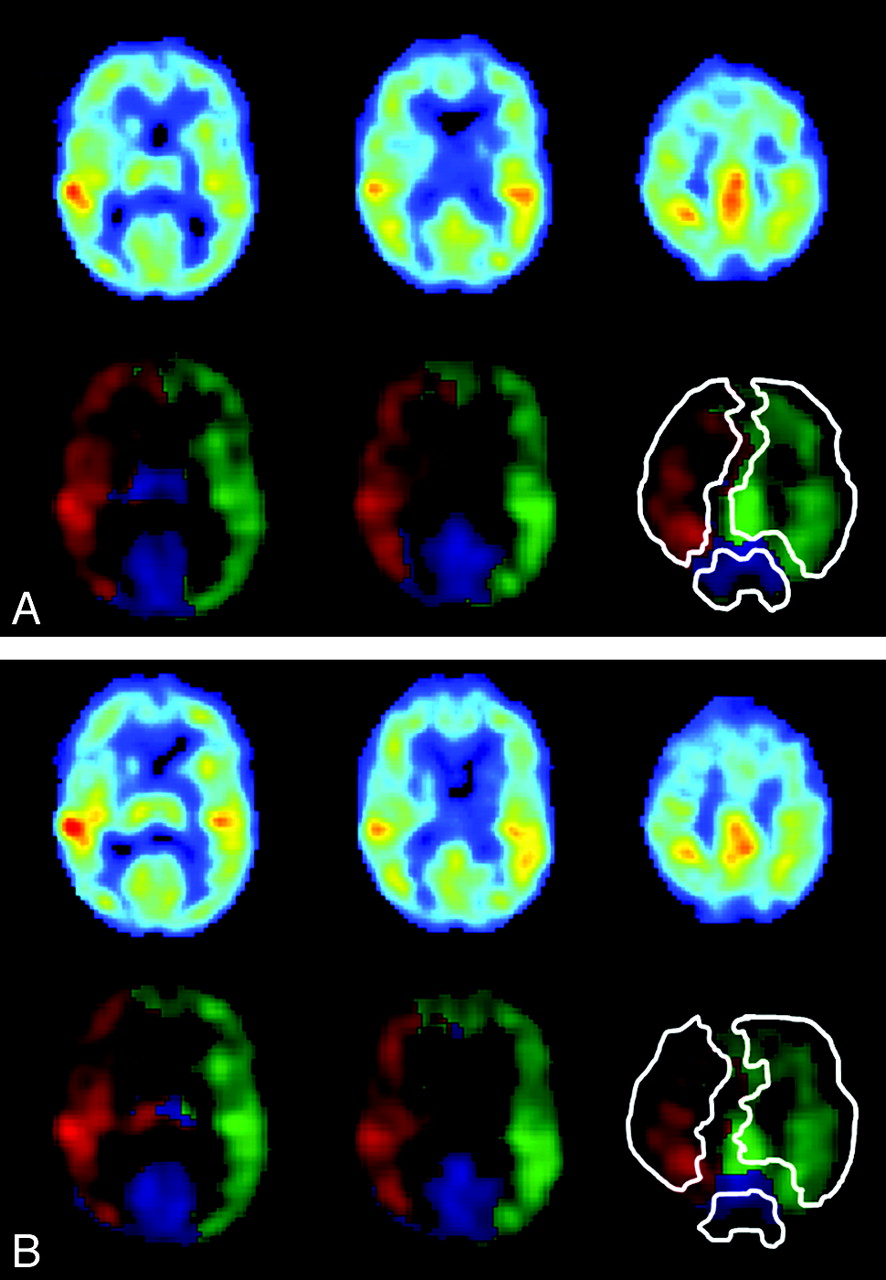

The nonselective perfusion-weighted image and flow territories of the ICAs and the BA obtained by planning-free selective ASL in a single subject are shown in Fig 2A, B. Intrasession repeated flow mapping yielded comparable flow territories for all controls (100%) and for 8 of 10 patients (80%). Figure 3 shows the flow territories based on the first and second halves of a selective ASL scan in an 80-year-old woman with a right ICA stenosis of 70%–99%. Intrasession repeated flow mapping yielded similar flow territories with enlargement of the contralateral left ICA flow territory, though some differences could be observed at the level of the basal ganglia. In 2 patients, gross motion artifacts led to uninterpretable flow-territory maps.

Three axial sections showing perfusion-weighted images, flow territories, and manual outlining of the ICAs and the BA in an 80-year-old female patient with right ICA stenosis of 70%–99%. A and B, Images are based on the first (A) and last (B) 35 dynamics.